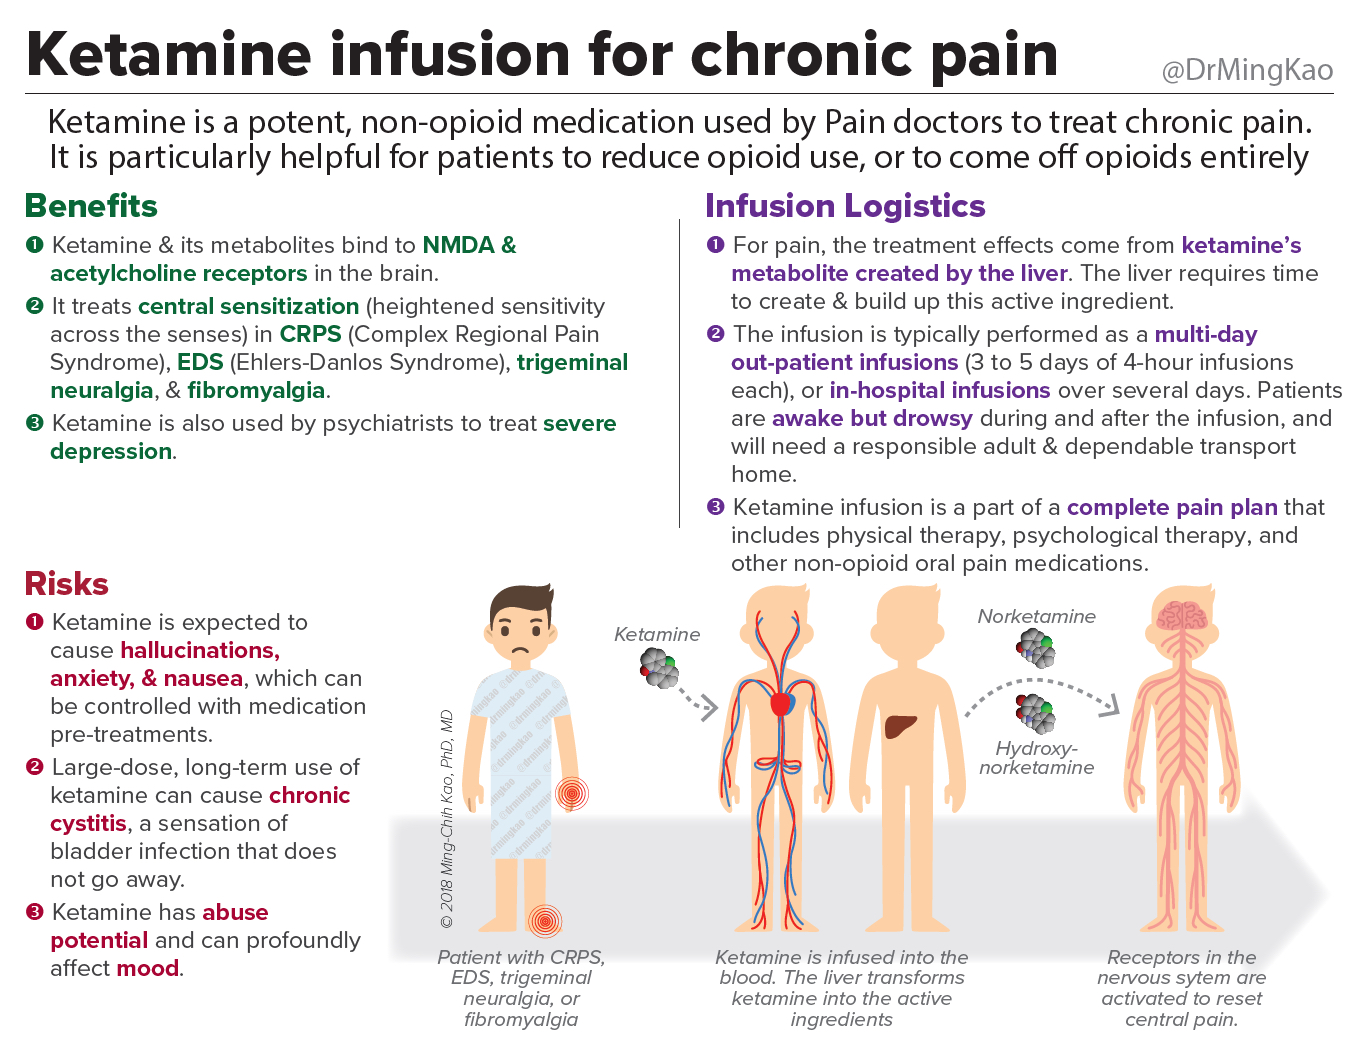

- Ketamine Infusions